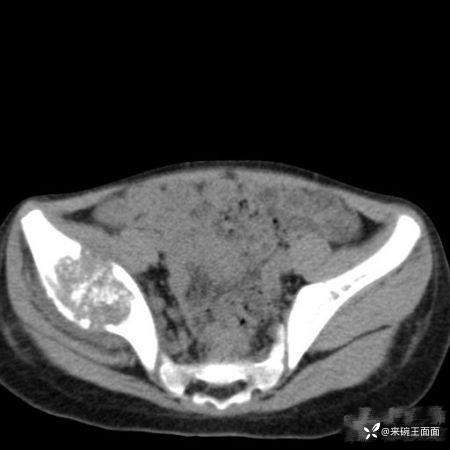

性别:女

年龄:6岁

主诉:跛行3年,右髋活动受限4月。

详情:右侧髂骨膨胀性骨质破坏,边缘有硬化,骨皮质不完整,有骨膜反应,可见边缘不清、形态不规则钙化、骨化影。